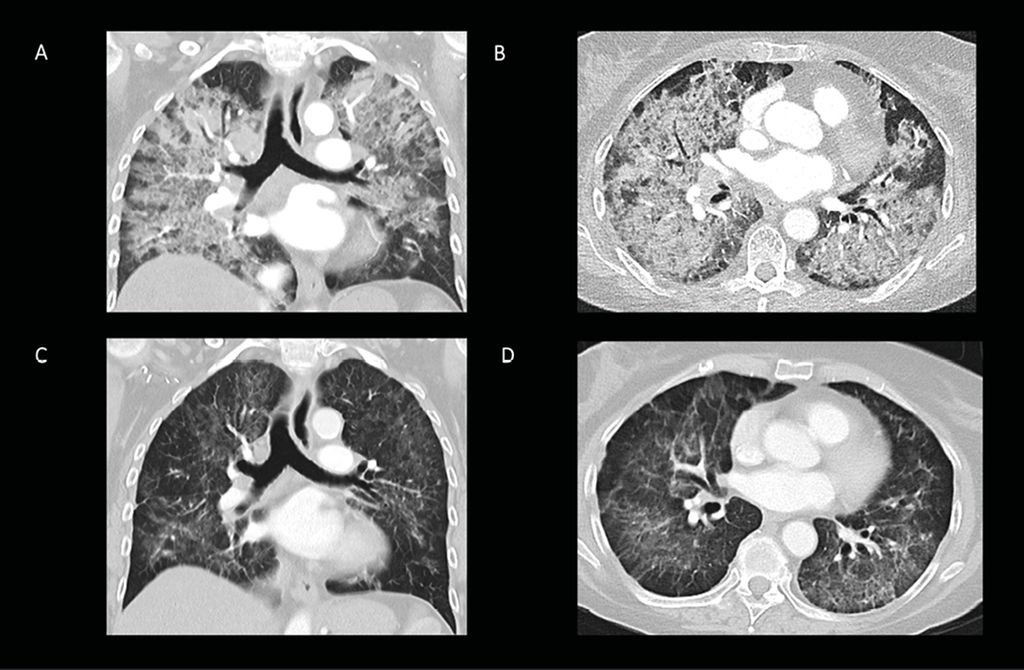

Eine 71-jährige Patientin stellt sich Mitte Dezember 2020 an der Notaufnahme aufgrund zunehmender Dyspnoe mit trockenem Husten und Fieber seit vier Wochen vor. Sie hat keine Lungenvorerkrankungen und ist Nieraucherin. Anamnestisch hat es einen rezenten Covid-19-Kontakt im häuslichen Umfeld gegeben. Klinisch entwickelt die Patientin eine rasch progrediente, hypoxämische Ateminsuffizienz mit einem Sauerstoffbedarf von 12l/min. Im Labor imponierten deutlich elevierte Entzündungsparameter mit Leukozyten von 12,75G/l, CRP von 29,8mg/dl sowie Interleukin6 von 261pg/ml, wobei das Procalcitonin im Normbereich lag. Außerdem war eine normozytäre und normochrome Anämie mit einem Hämoglobin von 6,9mg/dl auffällig. Im Thoraxröntgen fanden sich ausgedehnte, interstitiell kleinfleckige und peripher betonte Infiltrate in beiden Lungenhälften, wobei sichin der Thorax-CT eine massive alveoläre Anschoppung in allen Lungenabschnitten darstellen ließ (Abb. 1).

Abb. 1: A und B: CT-Thorax zum Zeitpunkt der Aufnahme mit disseminierter alveolärer Anschoppung in allen Lungenabschnitten. C und D: CT-Thorax zwei Wochen nach Therapie